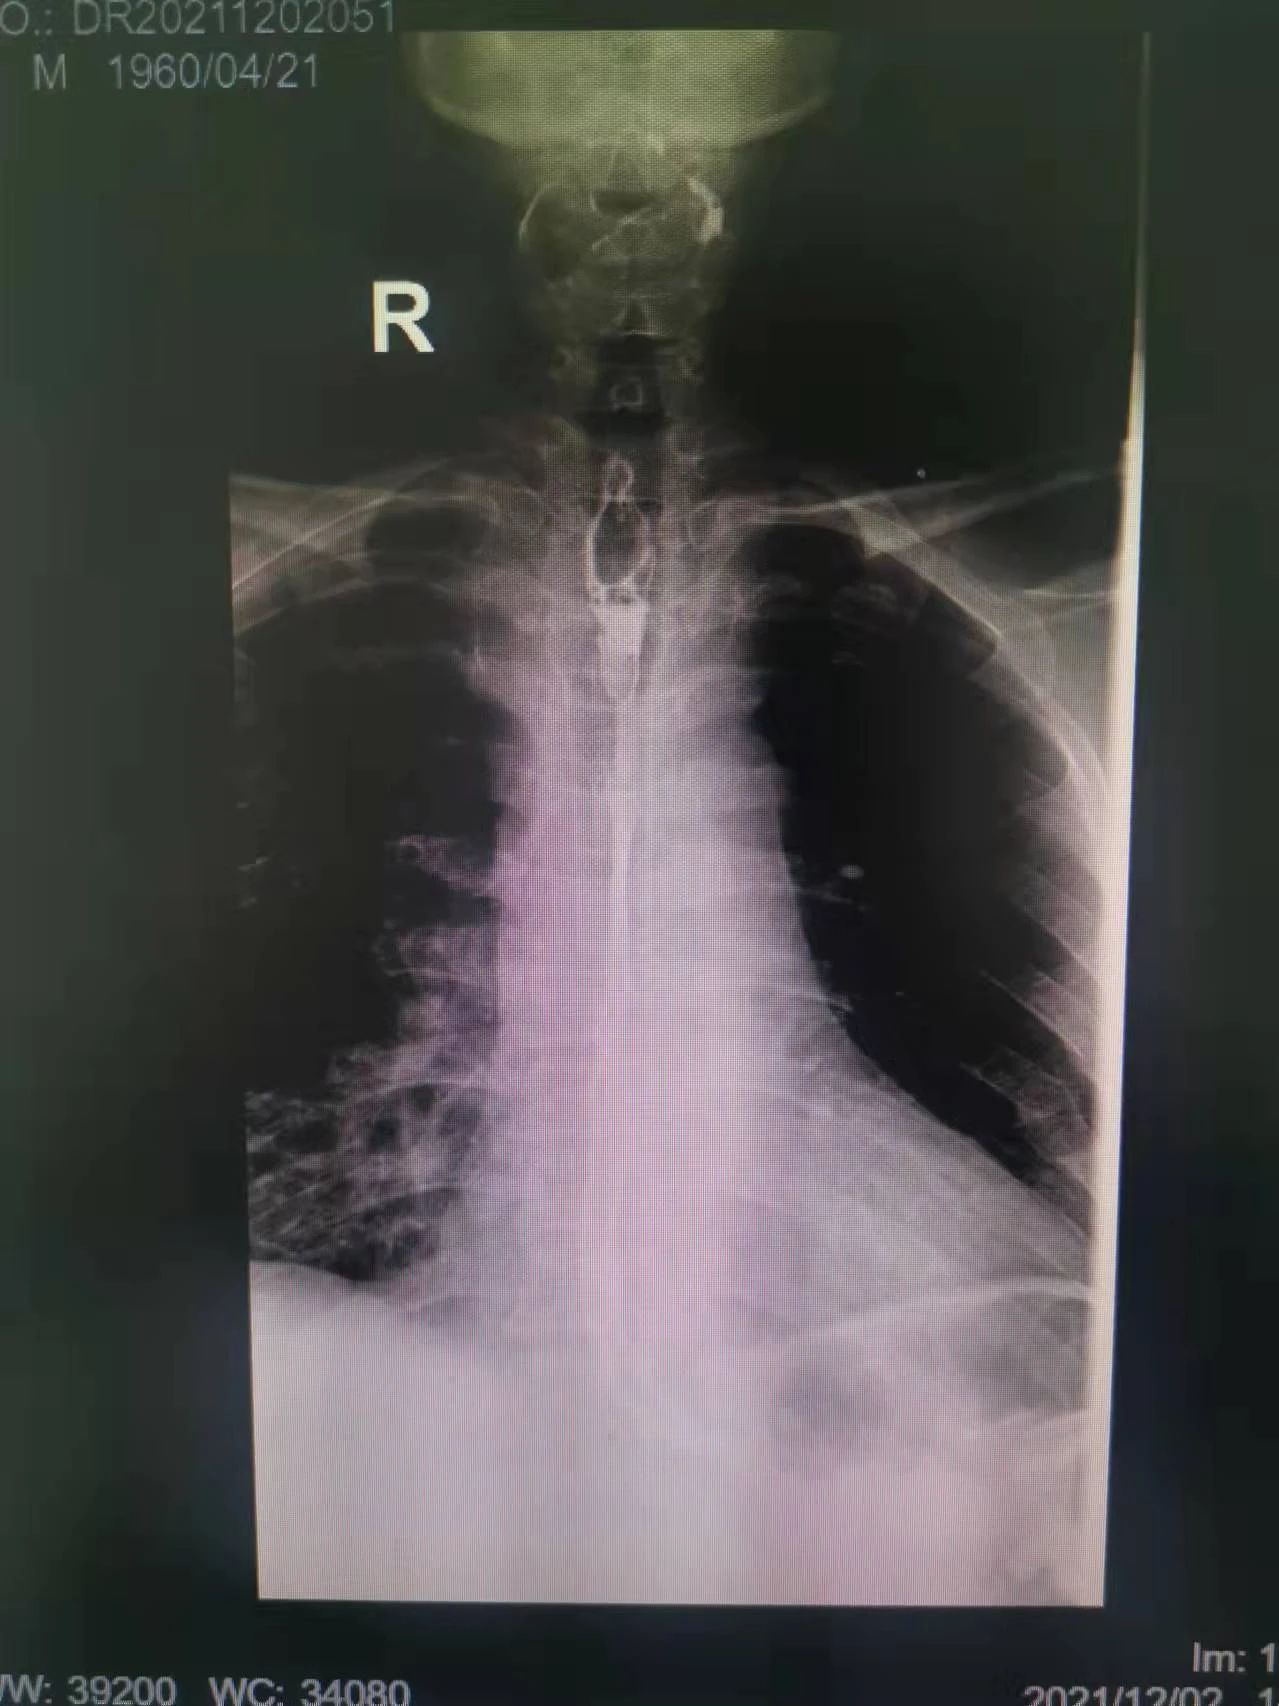

在這種情況下,我院介入二科侯主任決定通過介入治療中的食管支架植入來幫助患者實(shí)現(xiàn)這個愿望。手術(shù)當(dāng)日,侯主任在機(jī)器的幫助下,將一根細(xì)細(xì)的導(dǎo)絲穿過腫瘤到達(dá)付大爺胃部,然后再沿著導(dǎo)絲,把壓縮好的支架放在腫瘤里面。通過后撤導(dǎo)管,把壓縮的支架打開,支架把腫瘤撐開,讓食管不再堵塞。有了支架的支撐,付大爺就可以自由地吃東西了,哪怕食管和氣管有溝通,因?yàn)橹Ъ芨采w了腫瘤,通道堵住了,吃的東西也不會吸到肺內(nèi)造成感染。這時痛痛快快地吃上一頓,也不再是奢望!

手術(shù)很順利,付大爺也在術(shù)后第2天喝到了自己日思夜想的清水,露出了久違的笑容。從某種意義上講,介入食管支架置入術(shù)的成功實(shí)施,付大爺不能進(jìn)食的病已經(jīng)“治好”了,雖然從生理角度來說,付大爺可以通過終生使用腸內(nèi)營養(yǎng)來維持生存,但我們所做的是致力于給予患者更好的生存體驗(yàn),或者說是尊嚴(yán)。銘記并保持一名醫(yī)者的初心,我們要做的正如那句著名的墓志銘所說:有時去治愈,常常去幫助,總是去安慰。